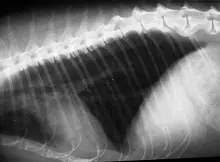

Prvi korak u dijagnostici jest rentgensko snimanje grudne šupljine, uz pretpostavku da pacijent nije toliko kritično da bi samo pozicioniranje i obuzdavanje moglo dodatno pogoršati stanje. Nalaz na plućima koji pokazuje tzv. „air-trapping“ (zadržavanje zraka) upućuje da se radi o astmi. Takav nalaz govori da je u plućima prisutna velika količina zraka koju je mačka udahnula no zbog suženja dišnih prohoda nije ga u mogućnosti izdahnuti. Rentgenski zbog povećanog volumena zraka u plućima ona se i doimaju veća.

Neke astmatične mačke mogu imati uredne RTG nalaze?! Istina. Obzirom da promjene na plućima nisu uvijek rentgenski vidljive, dijagnoza astme često zna biti krivo postavljenja. Ponekad dijagnostika zna biti kompleksnija te mora uključivati analizu stanica iz donjih dijelova dišnih prohoda mačke. Stanice se dobivaju postupkom koji nazivamo trahealno ispiranje koje se provodi u anesteziji, a ponekad je potrebno učiniti i bronhoskopiju.